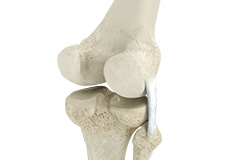

Bones of the Knee

The knee is a hinge joint made up of two bones, the thighbone (femur) and shinbone (tibia). There are two round knobs at the end of the femur called femoral condyles that articulate with the flat surface of the tibia called the tibial plateau. The tibial plateau on the inside of the leg is called the medial tibial plateau and on the outside of the leg, the lateral tibial plateau.

The two femoral condyles form a groove on the front (anterior) side of the knee called the patellofemoral groove. A small bone called the patella sits in this groove and forms the kneecap. It acts as a shield and protects the knee joint from direct trauma.

A fourth bone called the fibula is the other bone of the lower leg. This forms a small joint with the tibia. This joint has very little movement and is not considered a part of the main joint of the knee.